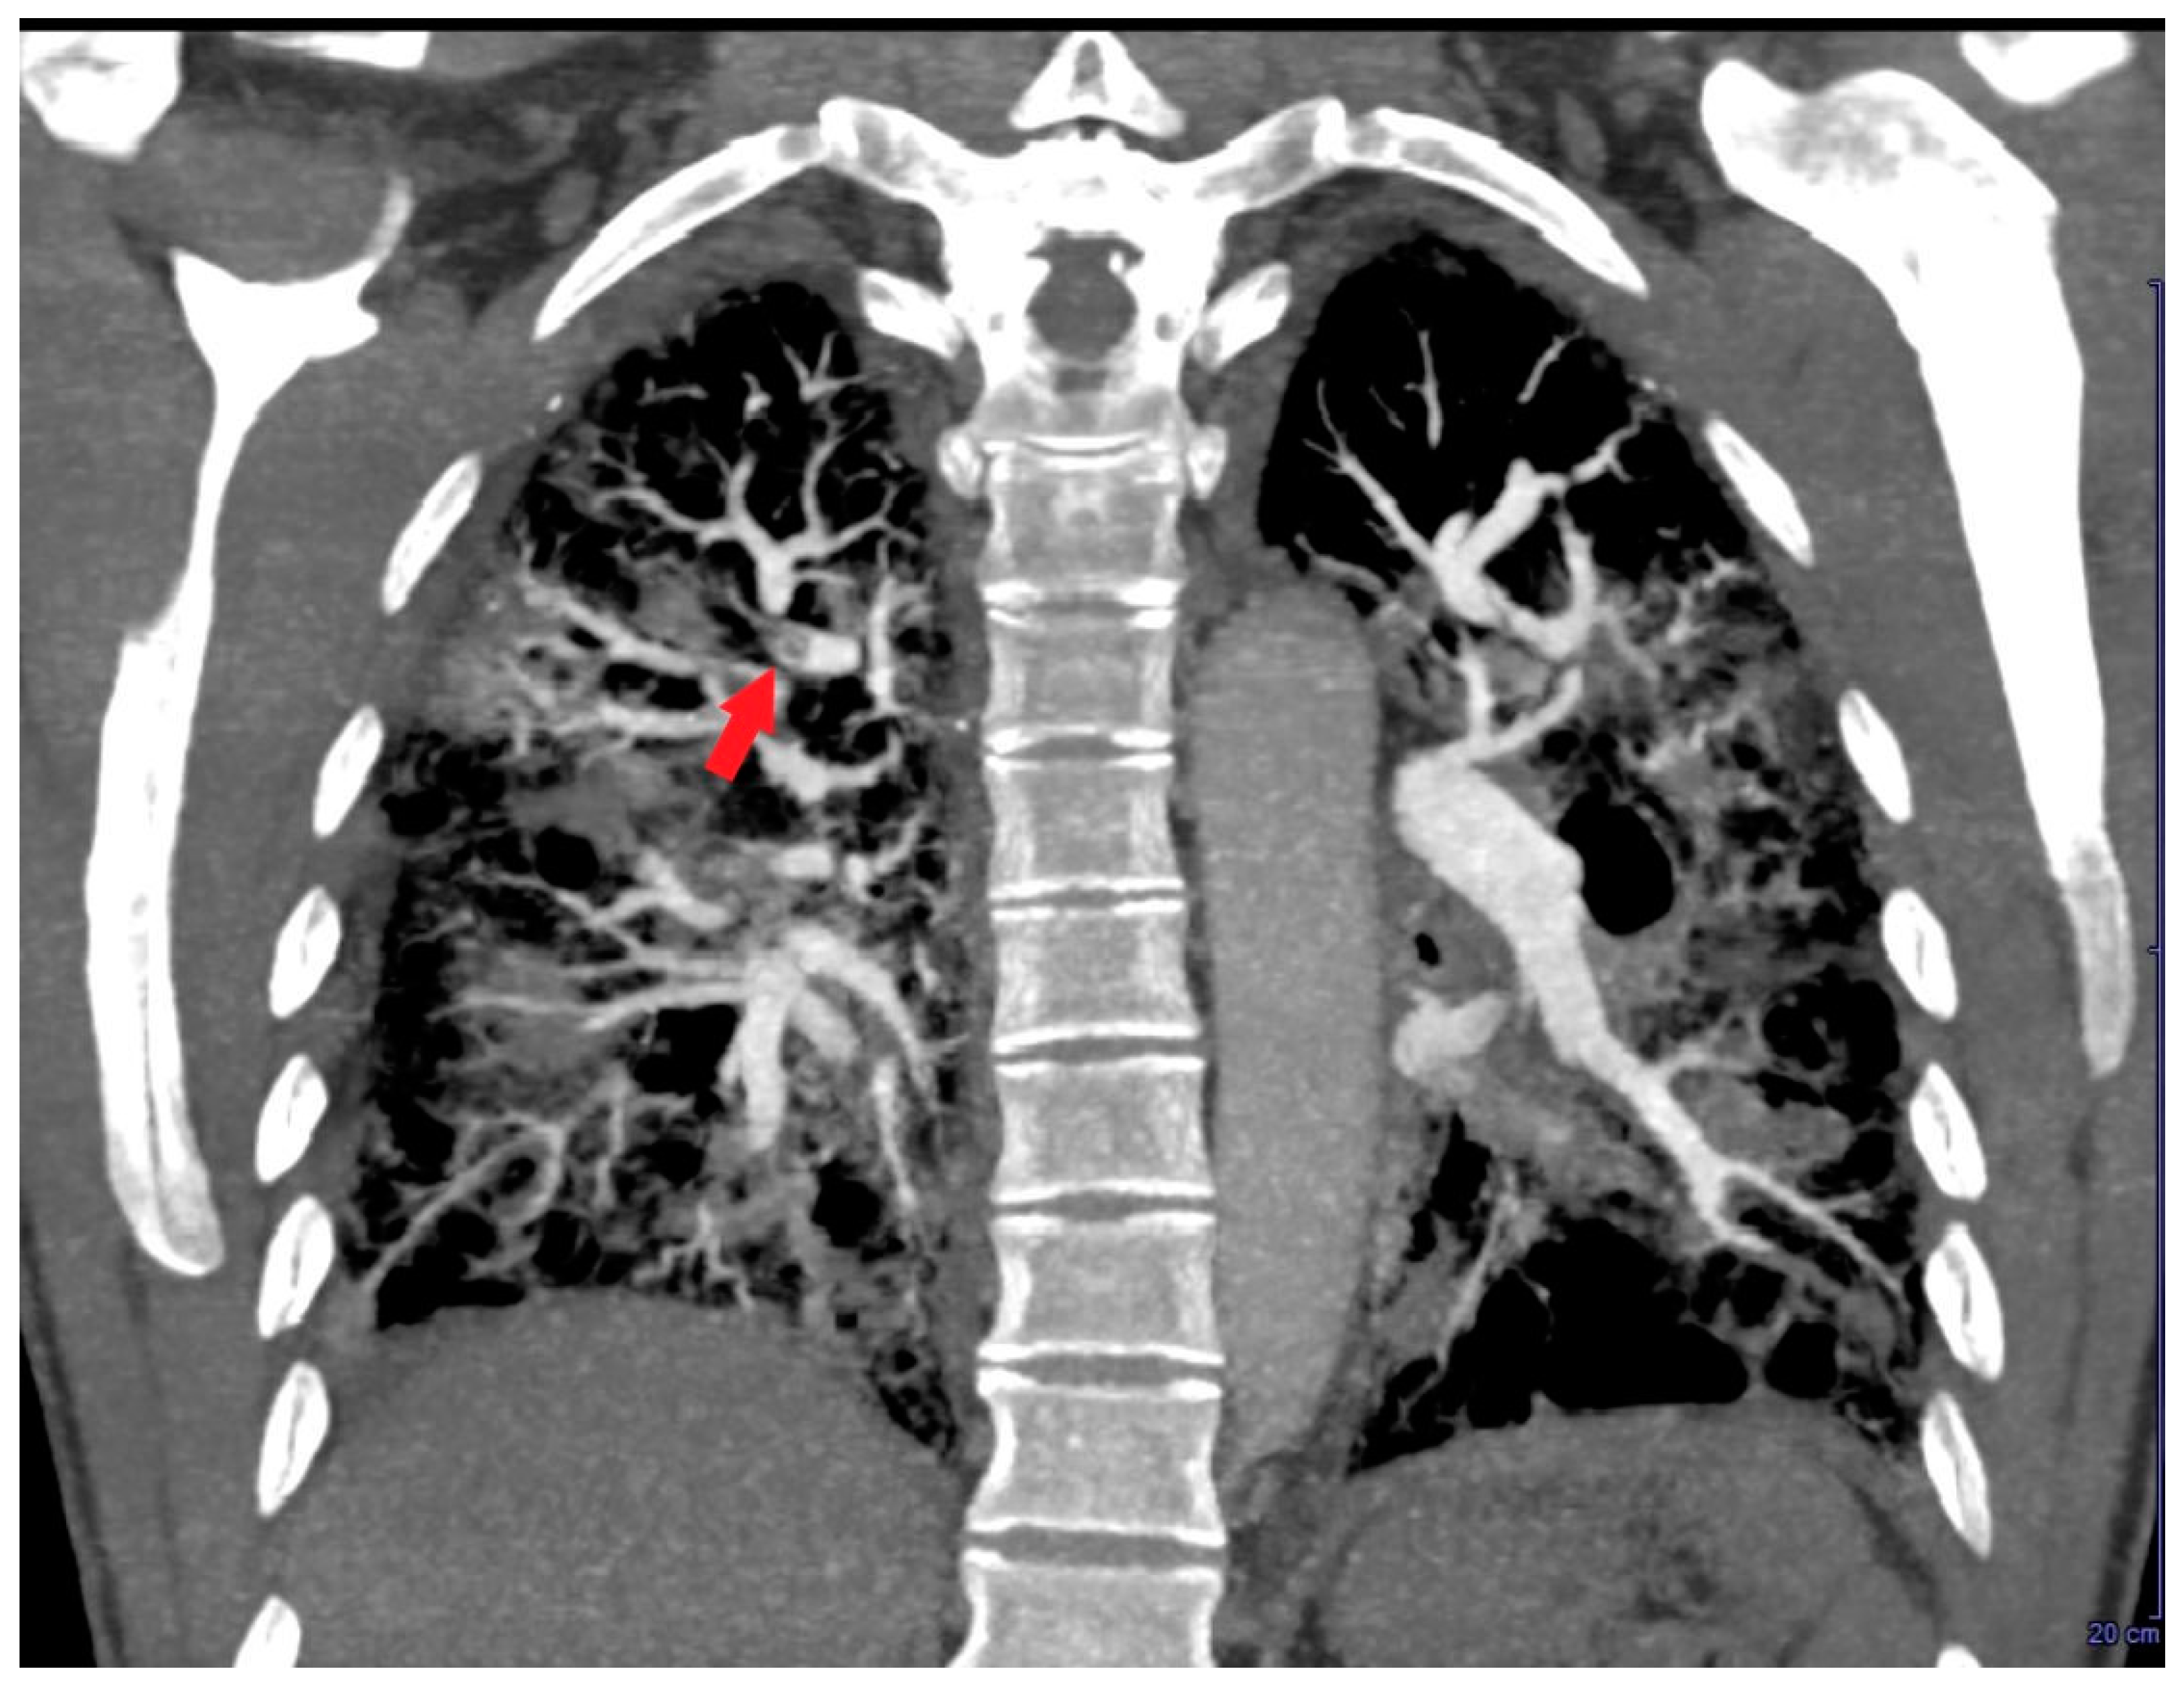

A further contrast-enhanced chest CT scan revealed segmental and subsegmental filling defects in the right upper lobe (Figure 6) and a concomitant mild reduction in RV mid-apical filling defect.

Figure 6. Coronal contrast-enhanced chest computed tomography revealing segmental and subsegmental filling defects (red arrow) in the right upper lobe.